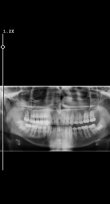

hayır hocam küçükken parmak emmişim biraz önde ama sıkıntı çıkarmıyor daha önce 2 doktara göründüm aşırı değil ilerde kötüye gitmez sen rahatsız oluyorsan yaptırabilirsin demişlerd hepsi öndede dğil ovallık varDişlerinde çapraşıklık var mı?